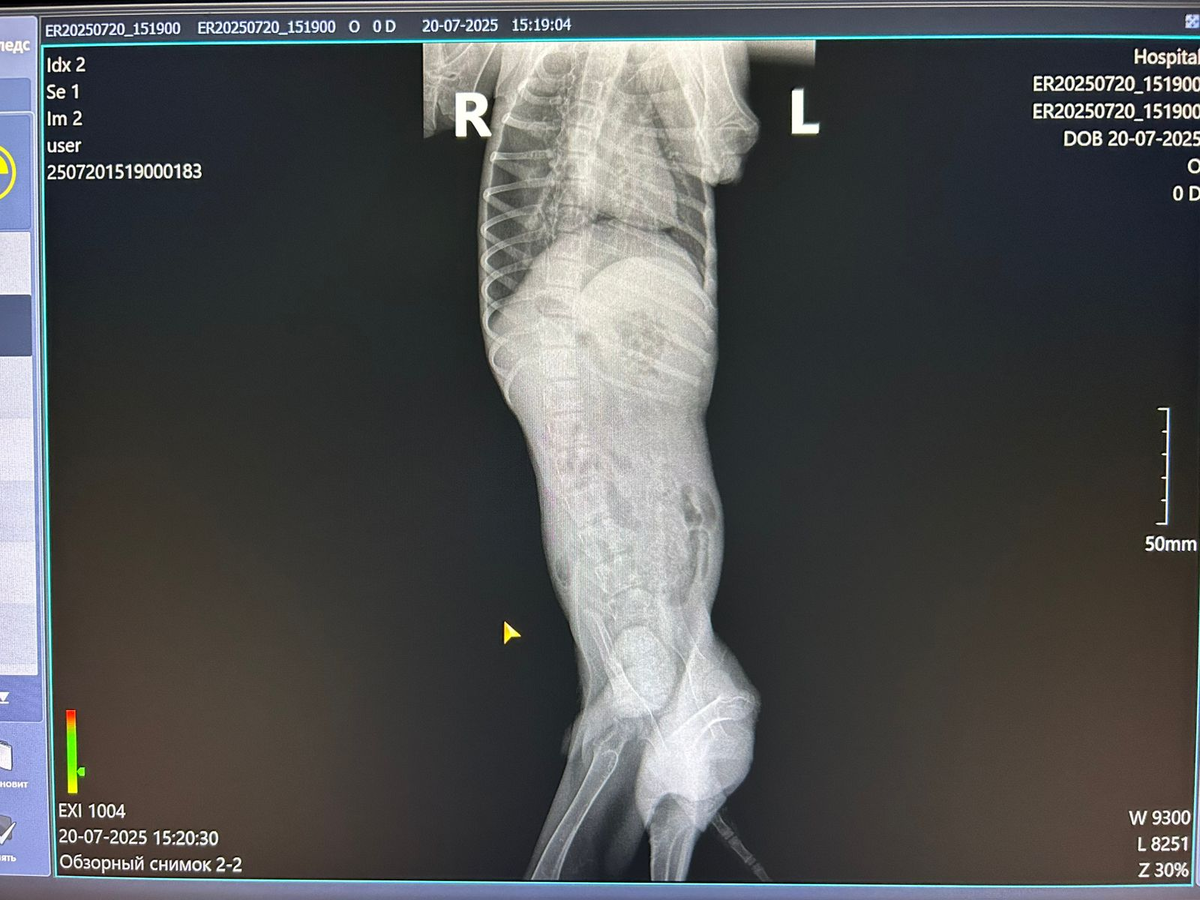

Дмитрий Викторович осмотрел, договорились, что будем орган спасать🙏🏻, как то ушивать, на всякий случай попросила сделать рентген, он сказал кости совсем прозрачные, у щенка кроме перелома в области таза, ещё и вторичный алиментарный гиперпаратериоз, другими словами, рахит, чувствительности так и нет, всё таки, спинальник, как и говорил врач при самом первом осмотре в клинике Альфавет.

Осмотр малыша Лелика в клинике Айболит перед операцией.